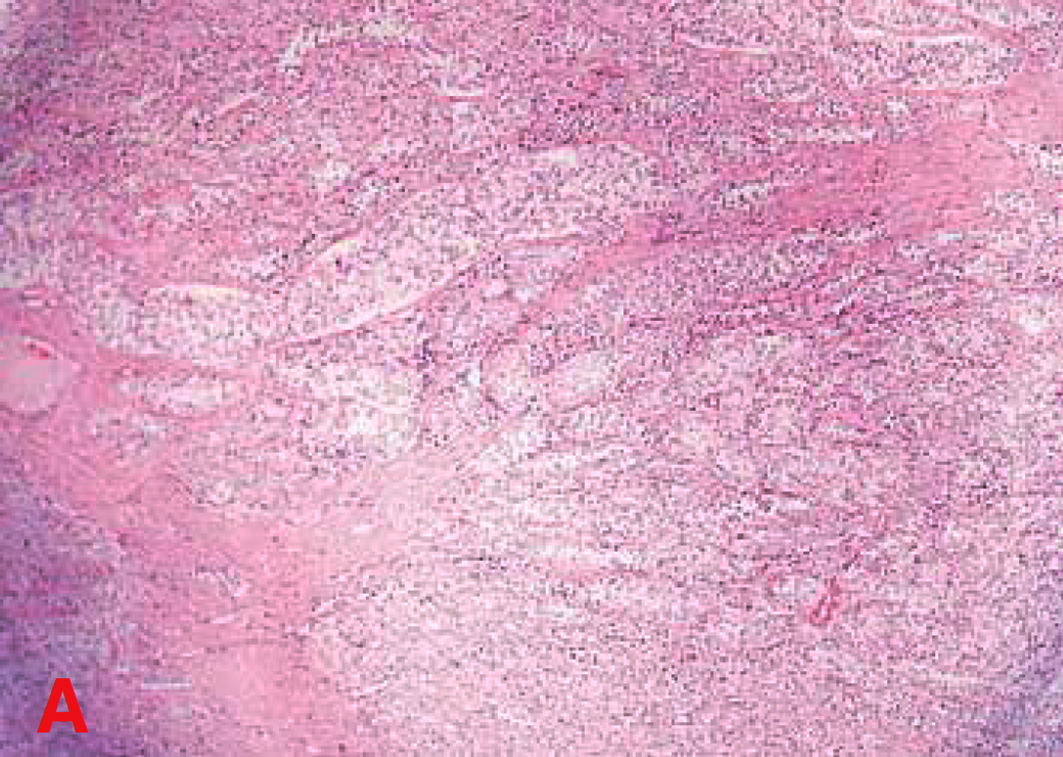

Na análise histopatológica do testículo criptorquídico, observou-se macroscopicamente superfície lisa e esbranquiçada, que ao corte era acastanhada. E o exame microscópico revelou uma proliferação de tecido epitelial composto por múltiplos lóbulos delineados por espesso estroma fibroso, apresentando estes diversos túbulos revestidos por células altas e cilíndricas, arranjadas em paliçada sobre a membrana basal, as quais apresentavam núcleos polares arredondados e nucléolos conspícuos (Figura 4). Os citoplasmas mostravam-se discretamente acidofílicos, com bordos pouco precisos. Figuras de mitoses atípicas foram visualizadas com baixa frequência. Tal descrição levou à conclusão de que se tratava de um sertolinoma.

Pela citologia aspirativa por agulha fina dos linfonodos e da próstata estabeleceu-se respectivamente o diagnóstico de processos metastáticos de sertolinoma (arranjos paliçados, citoplasmas macrovacuolizados e fusões de citoplasma, com formações paliçadas), além de metaplasia prostática 11,11.